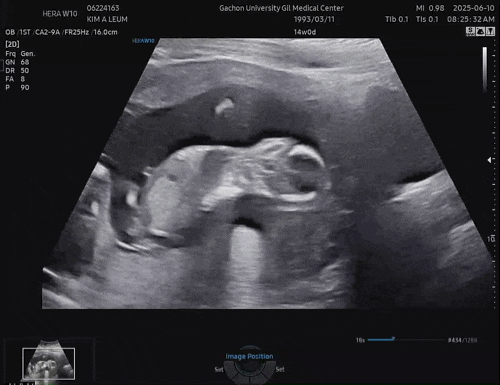

쌍둥이 임신13-14주차

나름 안정기로 가는 시기인건지 꽤 편안해진 요즘이다 ! 간지러움도 줄어 간헐적이고 울렁거리는것도 덜하...